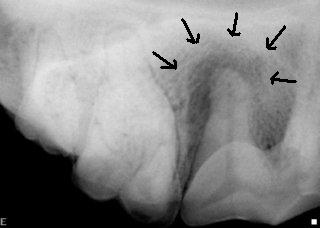

Dental radiographs of the dog on the left revealed a tooth fracture and root abscess associated with upper fourth premolar tooth.